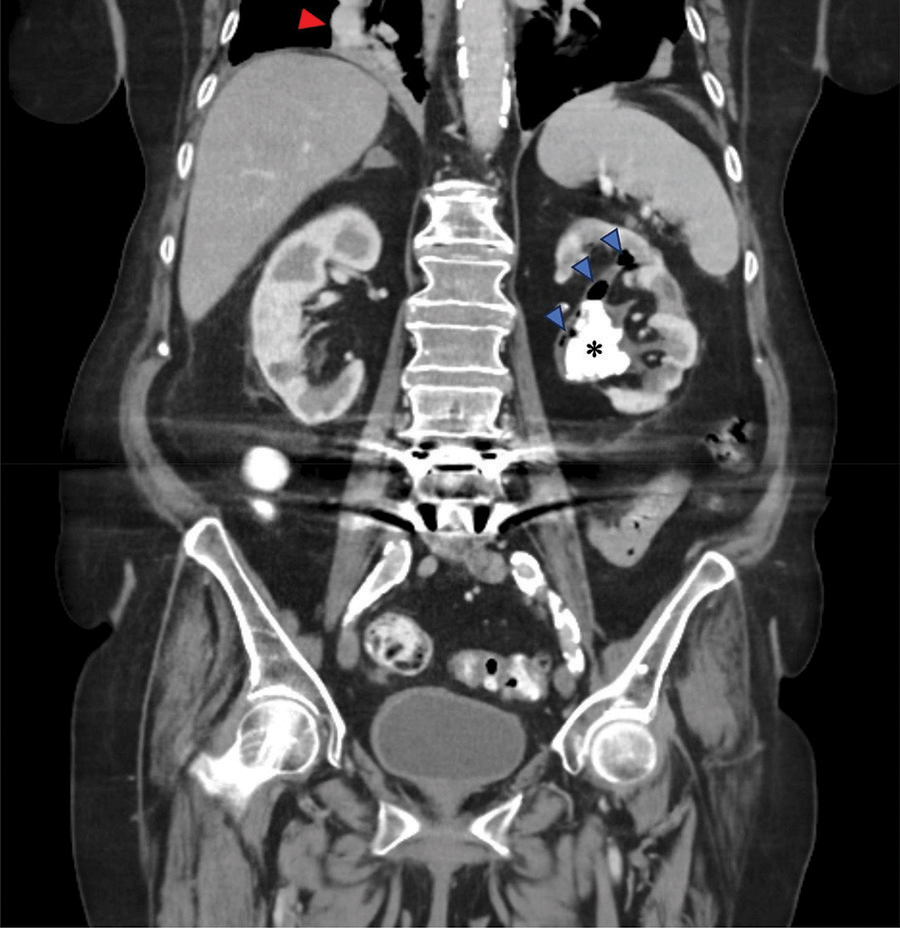

CT displayed a staghorn calculus (Figures 1 and 2, *) in the largely atrophic left kidney. There was a mild dilatation of the renal pelvis and calyces with wall thickening and multiple rounded fluid density cavities in the parenchyma. Gas bubbles were present in the renal pelvis surrounding the staghorn calculus (Figures 1 and 2, blue arrowheads). Some of the collections in the renal parenchyma contained gas-fluid levels (Figure 1, yellow arrows). A candidiasis infection (Candida glabrata >100 000 KVE/ml) was also identified on the urine culture test.

Figure 2

CT abdomen - coronal plane.

In addition, there was a diffusely thickened and hyperemic wall of the gallbladder, consistent with acute cholecystitis (Figure 1, red arrow). The right lower lobe pneumonia was depicted on the coronal view (Figure 2, red arrowhead).